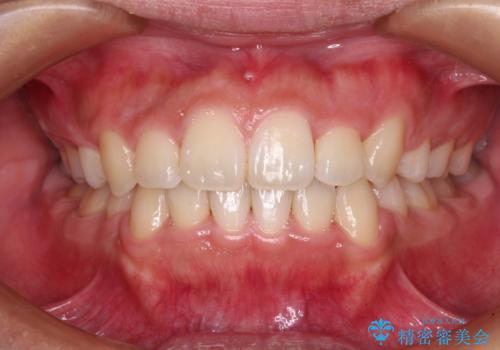

- 前歯のデコボコと口元の突出感を気にして来院された患者様です。

上下左右第一小臼歯4本を抜歯し、ワイヤー装置にて口元を引っ込めるよう矯正治療を行うこととしました。

非常にスムーズに歯列移動が行われ、当初は2-2.5年を予想していましたが、僅か1年4ヶ月で治療を終えることができました。